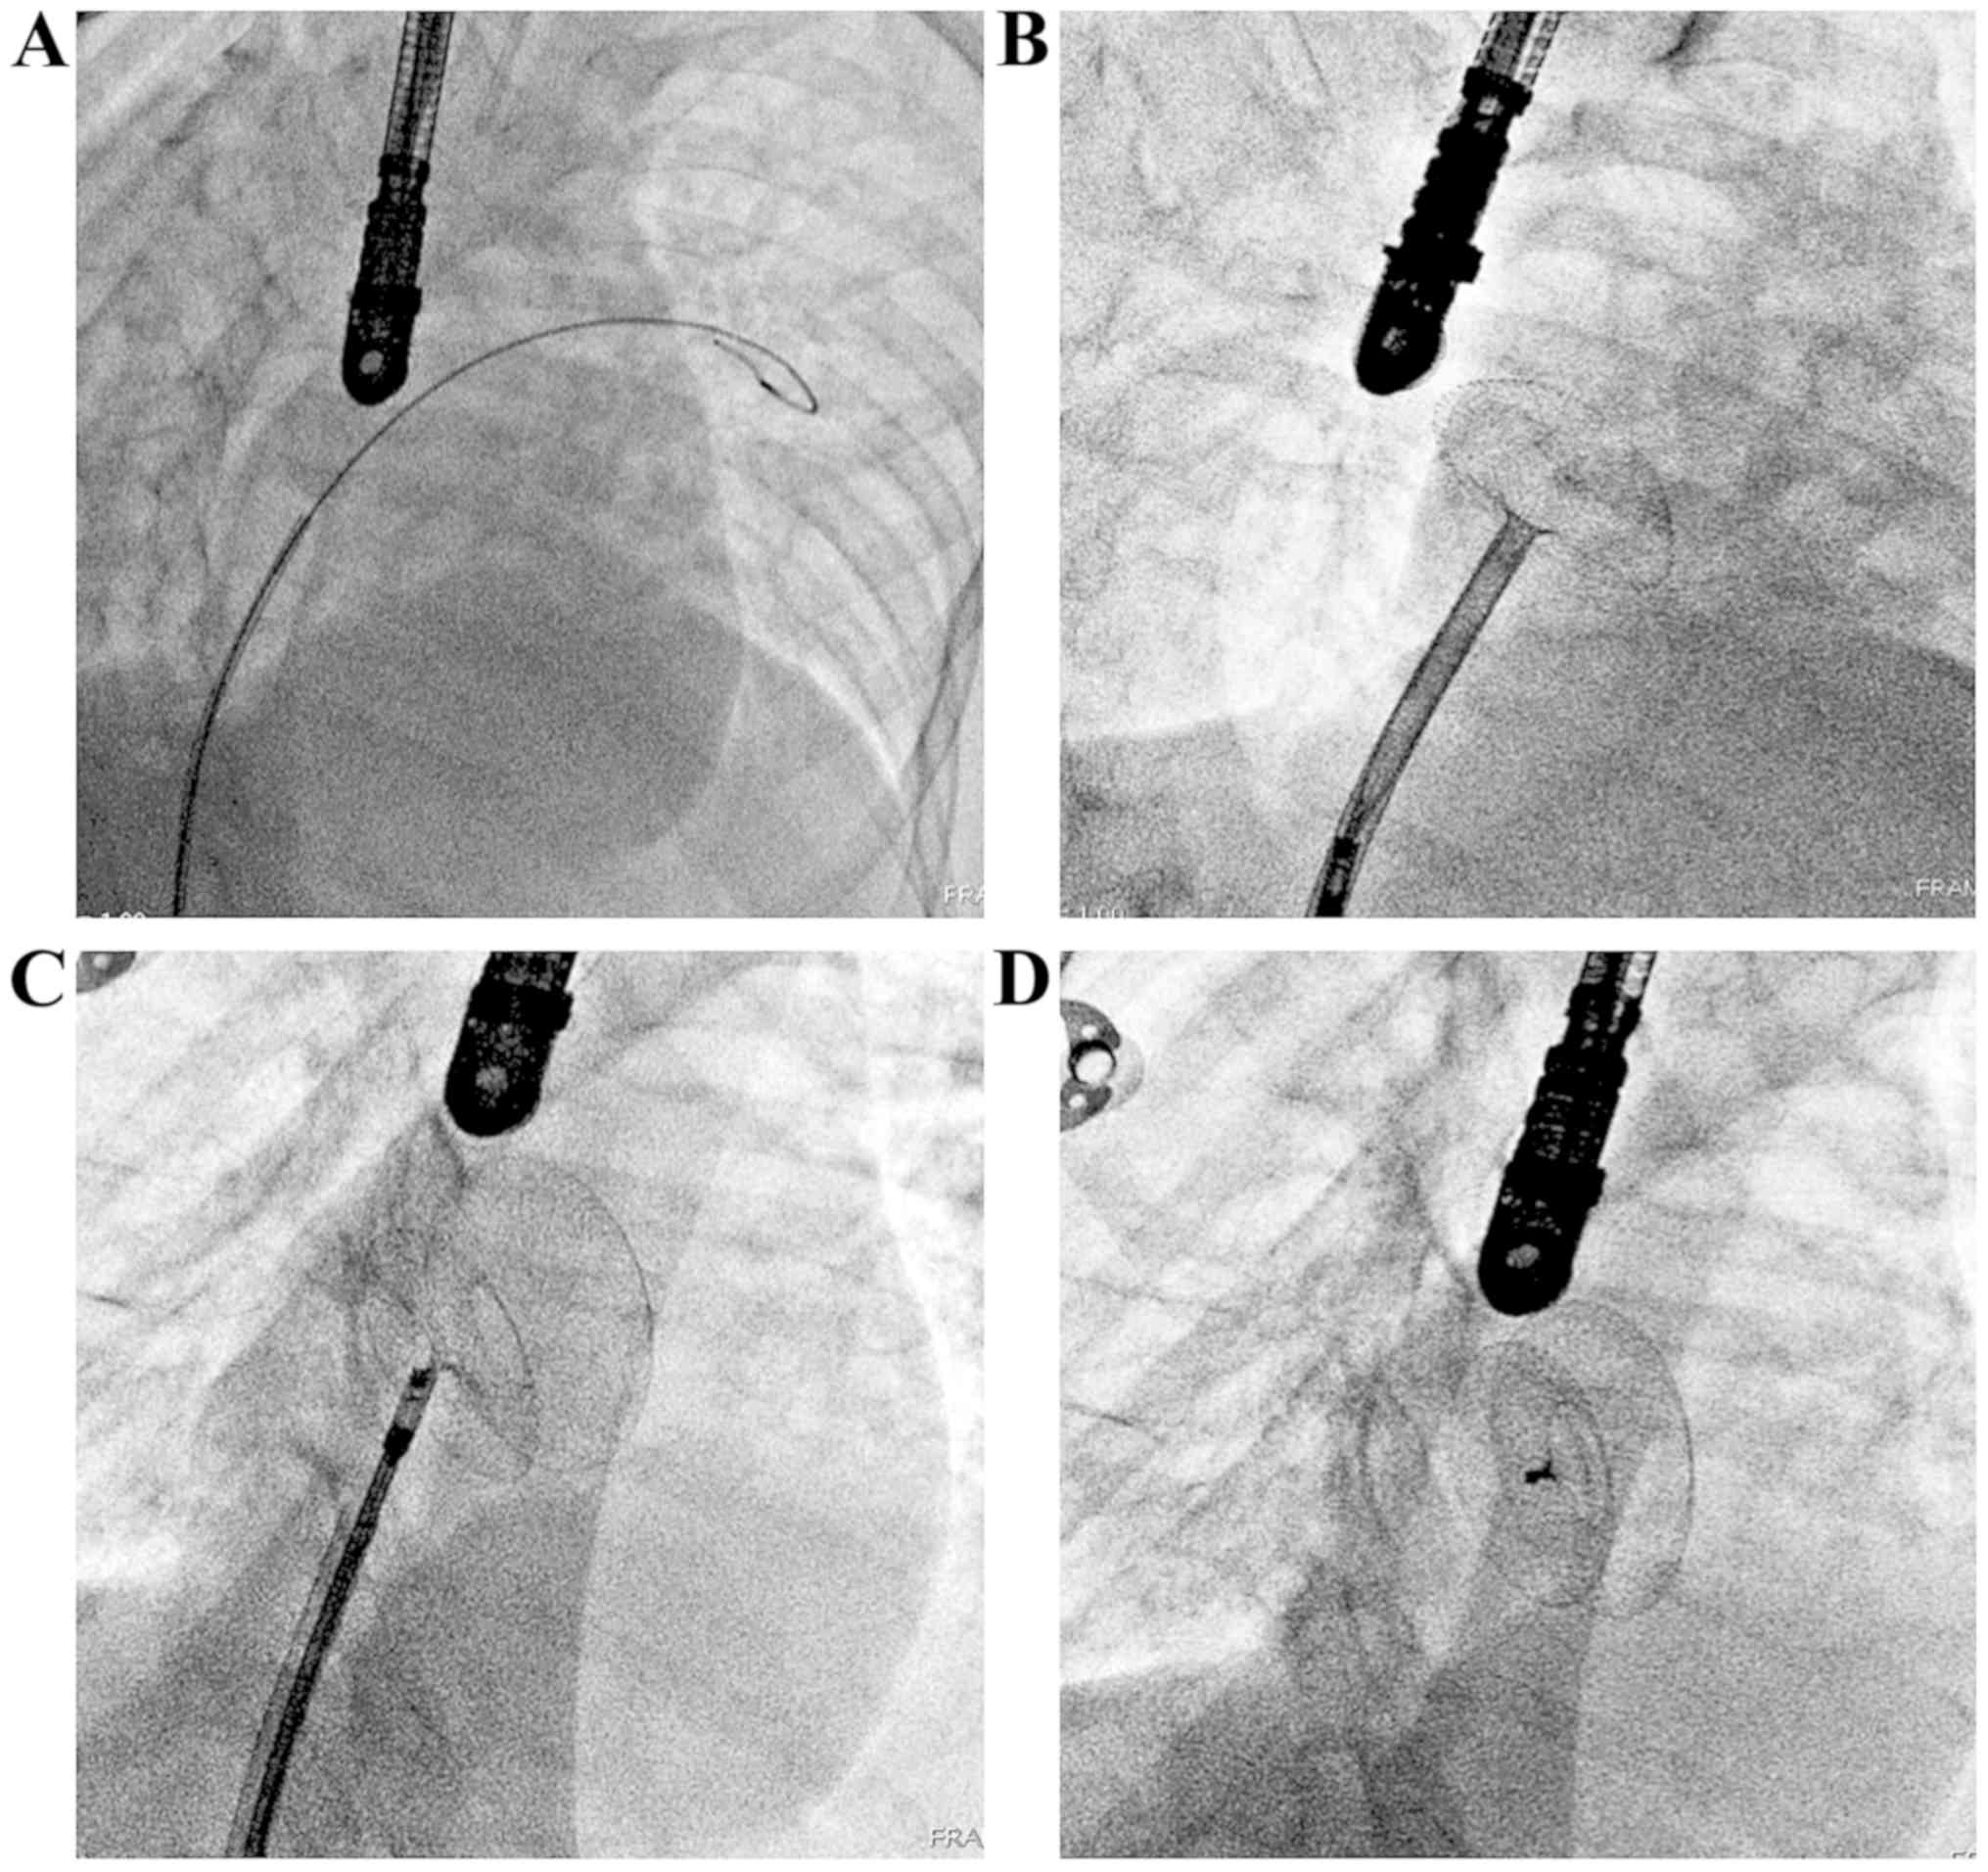

Device For Asd Closure : Fda Reports Serious Erosion Events With Amplatzer Septal Occluder Daic : Features are of a asd closure device that has been placed percutaneously.

The closure devices differ in design, but the placement method and their function are similar. (2) the china device has so far not been tested in clinical trials and the results achieved with the standard device cannot be. 2 asd/pfo closure amplatzer devices alpay celiker m.d. The possible mechanisms of the event and the options in management are discussed with a review of literature on all devices. This device is inserted through a catheter and covers the asd by attaching to the atrial septum. Trans catheter closure is feasible in anatomically complex substrates of secundum asd. Various devices for transcatheter asd closure are undergoing clinical trials. The amplatzer® septal occluder is a transcatheter closure device used to treat asds. Careful case selection, scrupulous imaging protocol, and expertise in modified techniques are mandatory for successful outcomes. Two different brands of closure devices are approved by the u.s. Www.3dechocardiography.com how to get the best imaging for asd and pfo closure. Features are of a asd closure device that has been placed percutaneously. The device was composed of two opposing umbrellas and since then different device designs have been studied.

Asd Closure Surgery In India Cost Of Asd Closure Surgery In India from www.besthearthospitalindia.com Two different brands of closure devices are approved by the u.s. Features are of a asd closure device that has been placed percutaneously. Transcatheter closure of ostium secundum atrial septal defect (asd) is a safe and eective procedure. The device was composed of two opposing umbrellas and since then different device designs have been studied. So far almost 10,000 devices have been implanted worldwide and its safety is established. The amplatzer septal occluder device. The closure devices differ in design, but the placement method and their function are similar. Careful case selection, scrupulous imaging protocol, and expertise in modified techniques are mandatory for successful outcomes.

Percutaneous closure of an asd is currently only indicated for the closure of secundum asds with a sufficient rim of tissue around the septal defect so that the closure device does not impinge upon the superior vena cava, inferior vena cava, or the tricuspid or mitral valves.